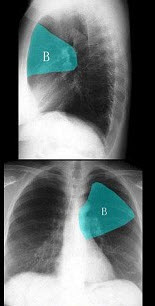

B.左上叶孤立性结节,类圆形,无分叶和毛刺,CT增强后明显强化

17、单项选择题

关于X线物理效应的说法,哪项是正确的()

a.穿透作用

b.电离作用

c.荧光作用

d.热作用

e.干涉与衍射作用

A.a,b,c

如图,在正常胸部X线影像图像上,该英文字母所代表的肺段为()

A.尖段

B.后段

C.尖后段

D.舌叶上段

E.前段